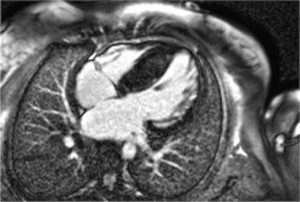

Immagine di RMN cardiaca

La Risonanza Magnetica Cardiaca (RMN) è un’indagine che utilizza un campo magnetico centrato sullo studio del cuore. Per alcune specifiche patologie cardiache la RMN è un esame fondamentale perché permette di acquisire immagini estremamente accurate e dettagliate sulle caratteristiche morfologiche e tissutali del cuore, fondamentali per precisare la diagnosi. Durante l’esame il paziente viene posizionato all’interno di un tubo, che contiene il magnete per un tempo variabile (da 30 minuti a 1 ora). E’ un esame con elevato profilo di sicurezza e non doloroso, ma occorre restare attivi. Attraverso appositi microfoni ed altoparlanti, il paziente è in comunicazione con il personale dedicato che impartirà ordini semplici come trattenere il respiro per un brevissimo periodo (solitamente 9-20 secondi) al fine di ottenere immagini ad alta definizione e prive di artefatti da movimento. Sul torace vengono applicati elettrodi per il monitoraggio del battito cardiaco e cuffie per isolare il paziente dai forti rumori generati dal magnete.

La RMN con mezzo di contrasto è fondamentale per capire se il muscolo cardiaco è ancora integro. Il mezzo di contrasto si accumula infatti nei tessuti danneggiati del cuore e permette quindi di riconoscere, dopo circa 10 minuti dalla sua somministrazione, zone cicatriziali (fibrosi), aree infiammate o infiltrate da altre sostanze dannose. La RMN cardiaca è l’unico esame che consente di visualizzare la presenza e stimare la quantità della fibrosi miocardica e della infiammazione del miocardio (miocardite).

La RMN può migliorare la visualizzazione delle strutture cardiache, ad esempio quando l’ecocardiogramma sia di difficile esecuzione (es. obesità o enfisema grave). Ma la RMN è fondamentale per precisare e valutare l’evoluzione del tipo di cardiomiopatia. In molte cardiomiopatie come ad esempio l’emocromatosi e l’amiloidosi cardiaca, fornisce anche informazioni sull’efficacia di terapie specifiche. La RMN può dare informazioni dettagliate sull’estensione della fibrosi miocardica, elemento che può essere importante per consigliare l’ eventuale impianto di defibrillatore. Infatti nei centri con maggiore esperienza, , è possibile stimare la percentuale di fibrosi rispetto alla massa cardiaca: se questa è superiore al 15% costituisce un elemento di rischio aggiuntivo per le aritmie ventricolari.

La RMN è la metodica di riferimento per la valutazione dei volumi, della funzione ventricolare sinistra, ma soprattutto destra, che non è facilmente analizzabile con l’ecocardiografia. Poi la RMN cardiaca è uno strumento diagnostico fondamentale che fornisce informazioni uniche sulla composizione del tessuto cardiaco e può consentire di precisare il tipo di cardiomiopatia e di iniziare una terapia specifica